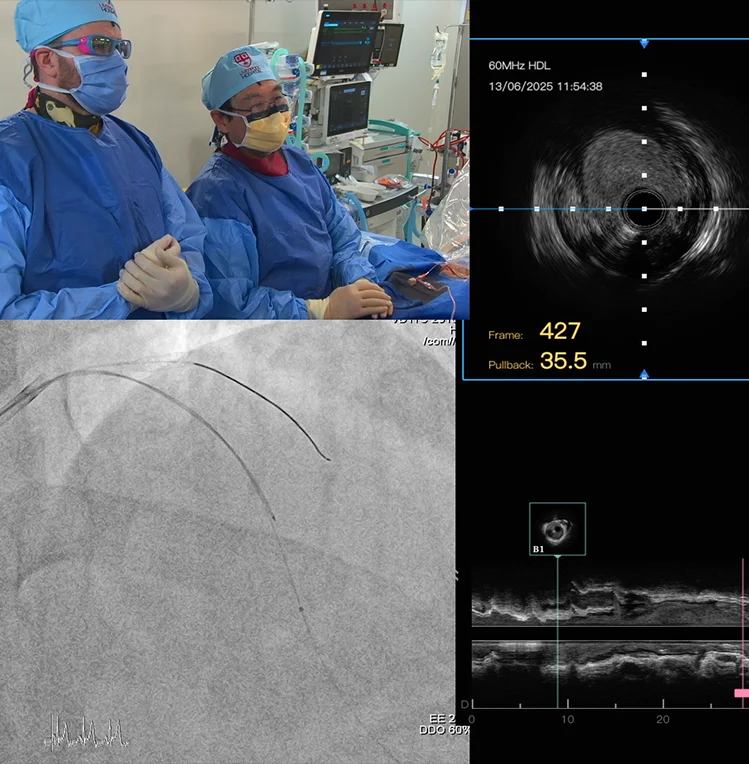

Live Medical Video Production

We provide seamless live streaming services for surgeries, conferences, lectures, and medical demonstrations. Using advanced equipment and secure streaming platforms, we ensure real-time, reliable delivery to local and global audiences. Our service enables remote participation, peer collaboration, and live education for healthcare teams and students.

Our crews have extensive experience in surgical environments and adhere to sterile protocols in operational Catheter Labs.